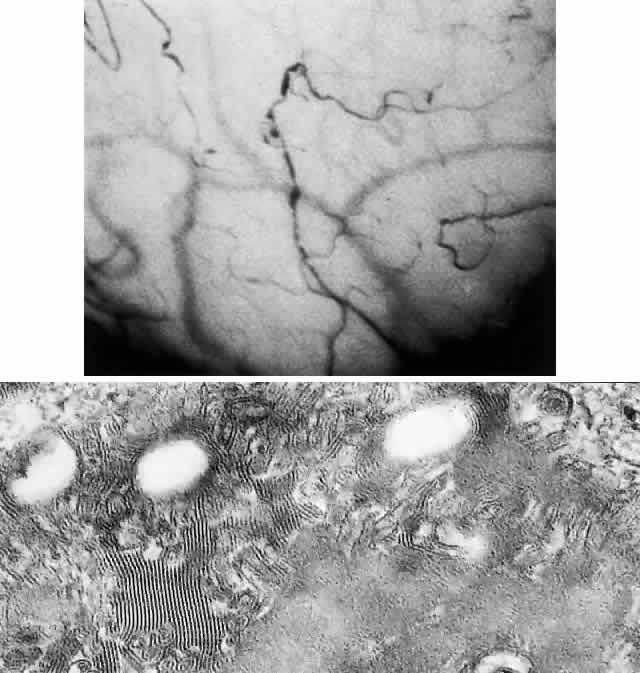

OCULAR FINDINGS. The outstanding clinical feature common to all three phenotypes is the corneal and conjunctival cystine crystal deposition (Figs. 3 and 4). Photophobia is often the only presenting visual symptom; this may be incapacitating and associated with blepharospasm.

Corneal deposits appear as a layer of homogeneously distributed, fusiform or needle-shaped, iridescent crystals situated in the stroma beneath the epithelium. In the infantile form, anterior crystal deposition begins early in life (between 6 and 15 months of age) and proceeds posteriorly as the patient ages; deposition advances more rapidly in the periphery. The anterior location of the crystals may be associated with recurrent erosions.33 The depth of the stromal deposition and the density of crystals is always greater peripherally than centrally. More and larger crystals occur in the superficial stroma. No visual impairment occurs at this early stage. By the age of 7 years, most patients have crystals, either within or on the endothelial surface34,35; markedly decreased corneal sensitivity is also present.36 The spherical contrast sensitivity function is significantly lower in infantile cystinosis than in age-matched controls.37

The retinal abnormality consists of a generalized depigmentation that may assume a patchy pattern. At first the pigmentary disturbance tends to be peripheral, but it progresses with age. Macular abnormalities have been observed.39 Intracellular crystals also have been seen in the retinal pigment epithelial cells during electron microscopy.